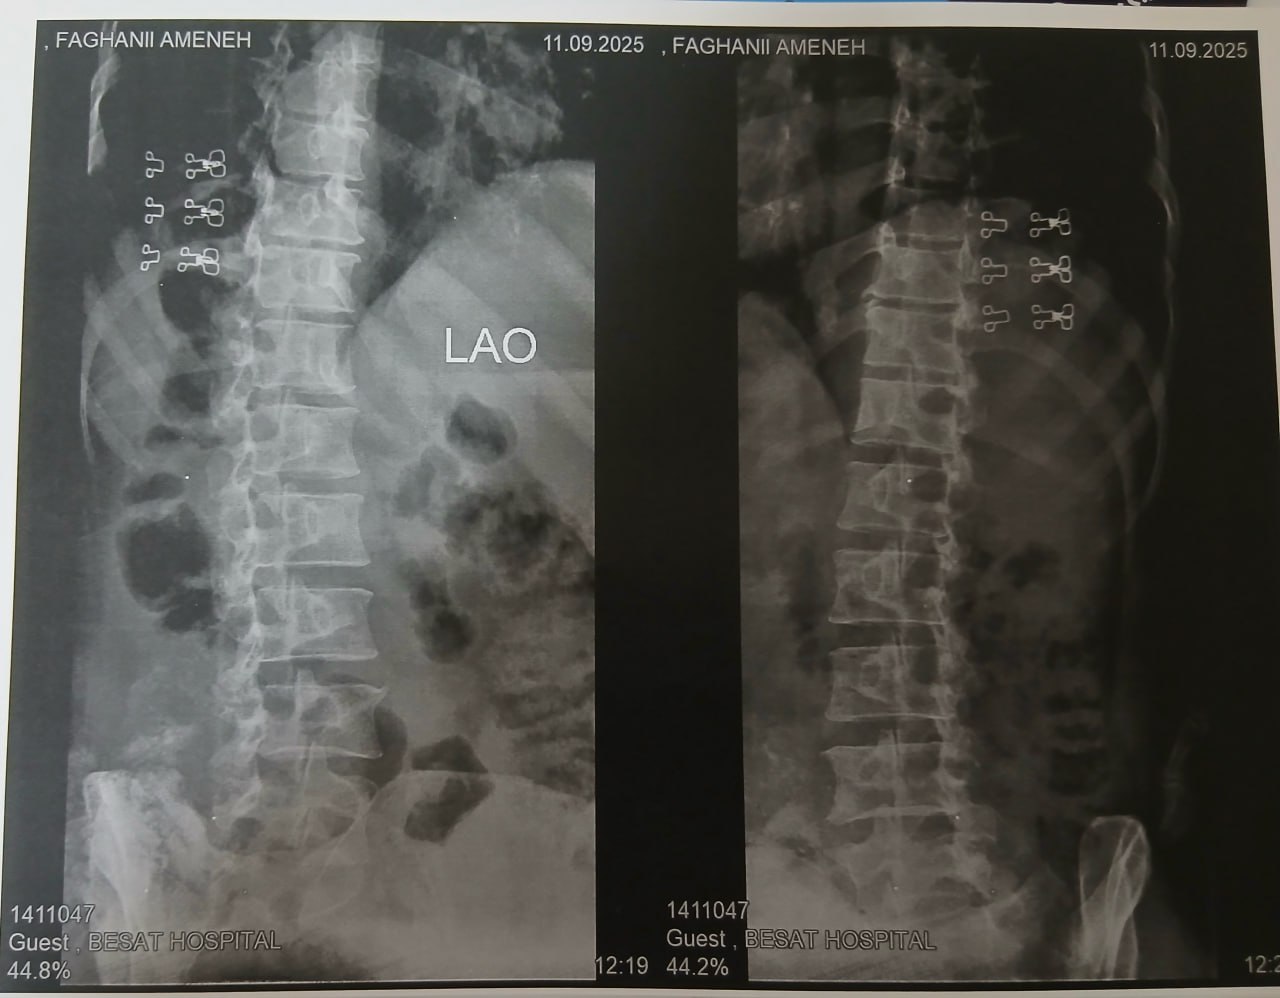

(تصویر مربوط به این مراجعه نیست) Other:

(تصویر مربوط به این مراجعه نیست) Other:

(تصویر مربوط به این مراجعه نیست) Other:

(تصویر مربوط به این مراجعه نیست) Other: